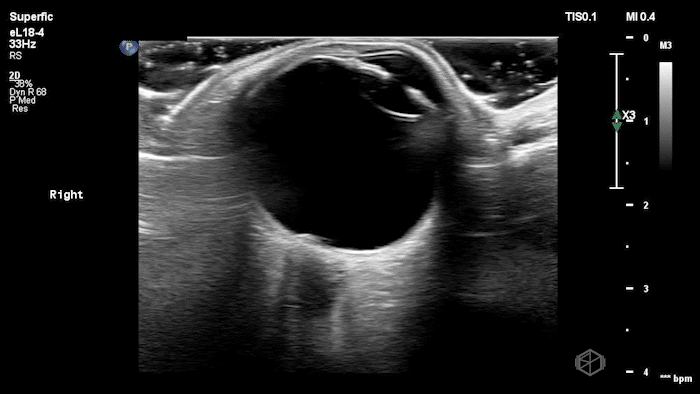

15 - What grade of hydronephrosis is this?

Severe hydronephrosis, cortical wall thinning is present.